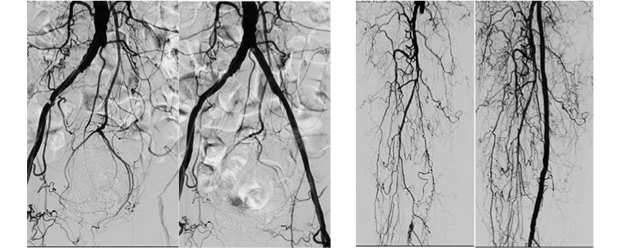

Endovascular Asia is a global multidisciplinary meeting. Our main focuses are total vascular care, peripheral artery disease and critical limb ischemia. Harmonization of endovascular therapy and wound care is also in our territory. This unique meeting has been evolved from Bay Area Endovascular Summit (BEST) to increase our friendship, expand the knowledge of vascular disease and sophisticate endovascular intervention for the treatment of Asian vascular disease patients.